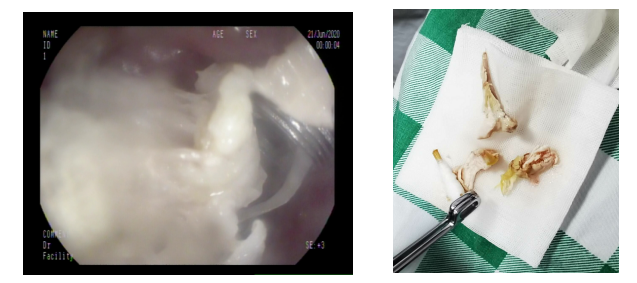

麻醉完成后,胃镜下可见食道上端入口处横卧着团块状食物堵住了整个食管入口,初步判断为鸡肉,距离门齿仅15cm。梁政主治医师在胃镜下通过活检钳、爪钳、圈套器试图把食物取出,初步判断为鸡肉。但因鸡肉块状已局部消化,难以整块取出,稍有不慎容易刺破食管或滑入气管,后果不堪设想,情况十分危急。

在消化内科梁政主治医师、麻醉科许永健主治医师、何少玲主管护师、以及马宗宝护师的合作下,鸡肉残渣及鸡骨被小心翼翼地顺利完整取出,经胃镜检查,未发现有新的粘膜受损。